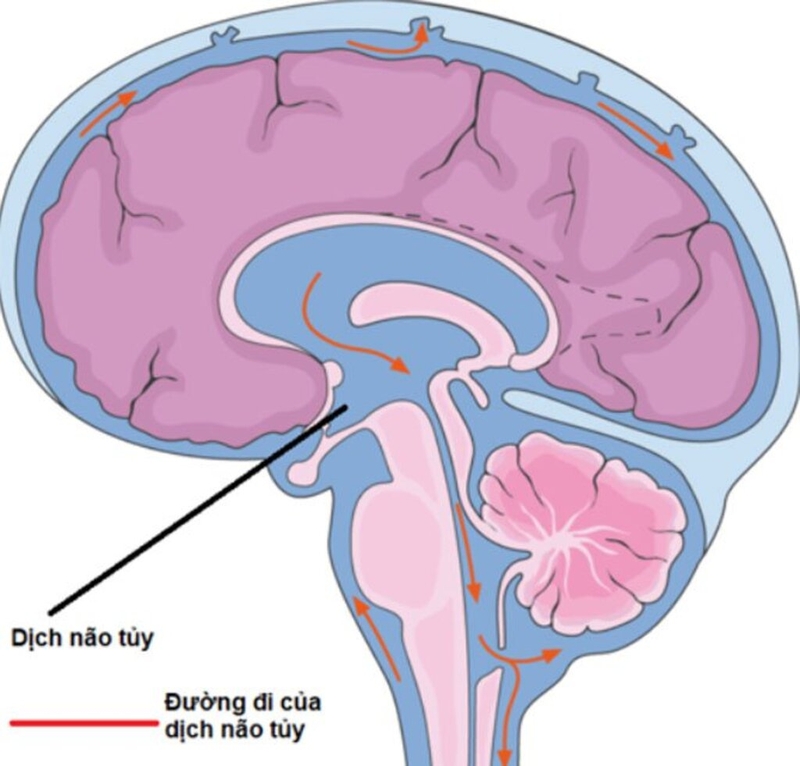

• Màng nuôi (hay còn gọi là màng mềm): Là lớp màng dính sát với tổ chức não, có nhiều mạch máu. Giữa màng nhện và màng mềm là khoang dưới nhện, có chứa dịch não tủy. Dịch não tủy là chất lỏng không màu, có tổng thể tích khoảng 130ml, có chức năng bảo vệ não tránh khỏi các chấn thương cơ học, nuôi dưỡng các mô thần kinh, đồng thời loại bỏ các sản phẩm chuyển hóa của hệ thần kinh.

Tìm hiểu nguyên nhân và biểu hiện thường gặp của người mắc hội chứng màng não 2 Dịch não tủy giúp chẩn đoán xác định hội chứng màng não